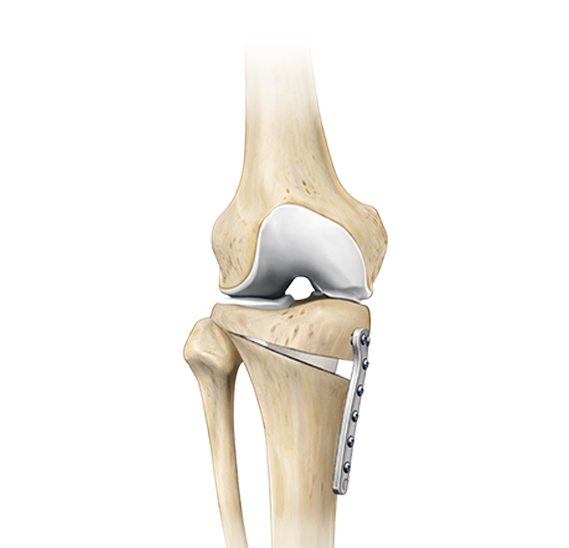

근위경골절골술은 오다리 변형으로 인해 무릎 안쪽 관절에 집중되는 체중 부하를 교정하기 위한 수술입니다.

무릎 아래 뼈인 경골의 정렬축을 조정하여, 이를 통해 무릎 안쪽 연골에 집중되던 부담을 줄이고 통증 완화를 기대할 수 있습니다.